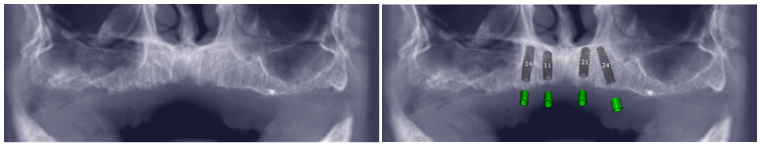

O planejamento das partes cirúrgicas e protéticas foram realizados após os exames tomográficos. Os arquivos DICOM e STL foram convertidos para o formato Blue Sky Plan (Blue Sky Bio-Libertyville, Illinois, EUA) e, através do Exocad, foi realizado todo o planejamento reverso e o posicionamento tridimensional dos objetos, bem como o planejamento da guia cirúrgica com os pinos de fixação. Portanto, este recurso possibilitou o planejamento da colocação dos implantes em suas posições ideais, respeitando as angulações e as estruturas anatômicas nobres, guiado pelo software.

Planejamento tridimensional dos implantes e da guia cirúrgica por meio do Exocad.

Conforme o plano de tratamento, os implantes estariam localizados nas regiões correspondentes aos dentes 11, 14, 21 e 24, utilizando a técnica All-on-4. Os implantes utilizados foram da Implacil De Bortoli: Due Cone – Maestro CM Base T 4.5 Ø 3,5x11mm para os incisivos centrais e Ø 3,5x13mm para os pré-molares.